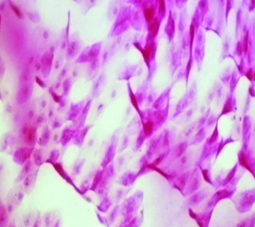

La citología de impresión (Fig. 16) permite identificar los cambios metaplásicos experimentados por la superficie epitelial conjuntival como consecuencia del ojo seco e identificar las características histológicas de las células mucosecretantes y de otras células que conforman a la superficie epitelial conjuntiva.

Figura 16: Citología de impresión

Permite diferenciar cuadros de ojo seco, de alergia, de disfunción de glándula de Meibomio, de toxicidad y realizar un correcto diagnóstico diferencial. Estudios comparativos con biopsia labial de pacientes portadores de Síndrome de Sjögren 22 le dan un gran valor diagnóstico de esa enfermedad.

Es de gran utilidad para diagnosticar disfunciones límbicas.